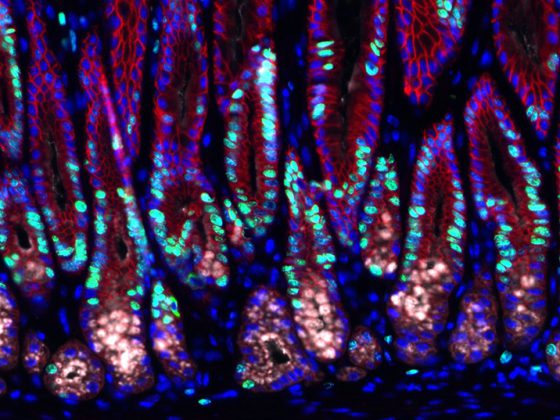

Leberkrebs ist die dritthäufigste krebsbedingte Todesursache weltweit. Bislang sind die Behandlungsmöglichkeiten von zwei Leberkrebsarten, das hepatozelluläre Karzinom (HCC) und das Cholangiokarzinom (CCA), unzureichend, bei zugleich steigender Tendenz an Neuerkrankungen. Hoffnung macht nun eine Studie von Forschenden der Medizinischen Hochschule Hannover (MHH) und des Helmholtz-Zentrums für Infektionsforschung (HZI). Ein Impfstoff auf Basis eines stark abgeschwächten Infektionserregers namens Listeria monocytogenes erwies sich in präklinischen Mausmodellen als sicherer und wirksamer Schutz bei prämalignen und malignen Lebererkrankungen.